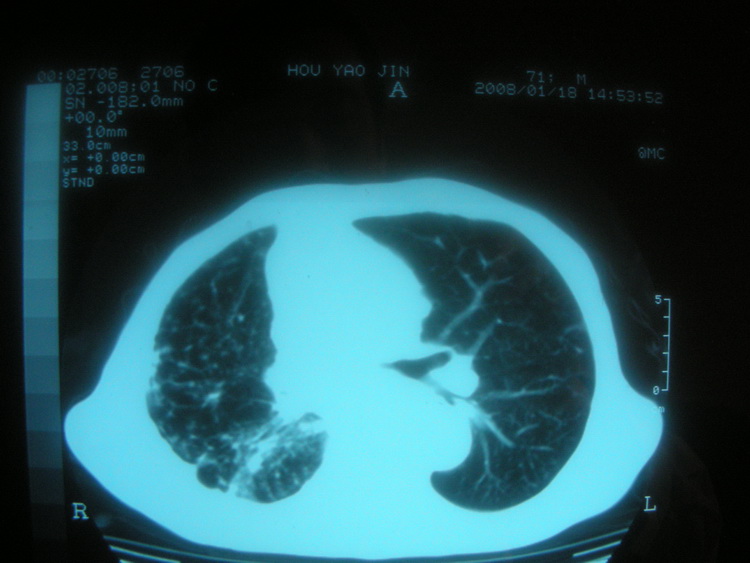

以下是引用卜一在2008-2-16 6:10:00的发言:[br]右肾增大,实质内明显见占位性病灶,并突出体外,密度不均匀。另双肺上叶见散在的斑片 索条及点状结节样致密影,右下肺门区不规则团块,右侧胸腔积液并形成局限性气胸。考虑:1 右肾癌。2 右肺门淋巴结转移及肺内 胸膜转移。3 右上肺陈旧结核。